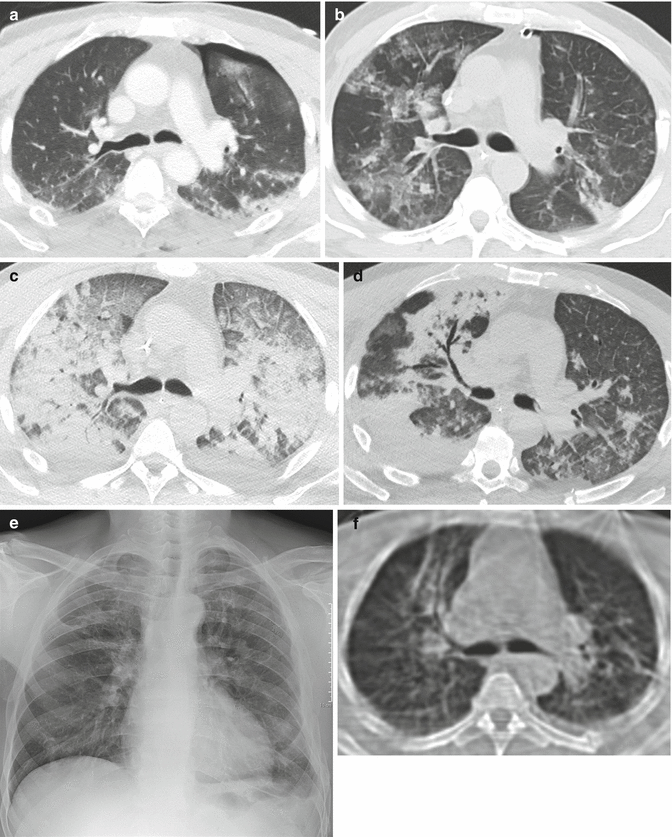

Chest HRCT scan (lung parenchymal window settings) at the level of the What Is Lung Parenchyma Definition Lung parenchyma is formed from millions of interdependent alveoli, which share the alveolar volume throughout the lung, preventing. The lung parenchyma denotes alveolar tissue with respiratory bronchioles, alveolar ducts, and terminal bronchioles, and often includes any form of lung. Continuum mechanics analysis of the lung parenchyma allows the prediction of the pressure outside the airway, but in most situations this.. What Is Lung Parenchyma Definition.